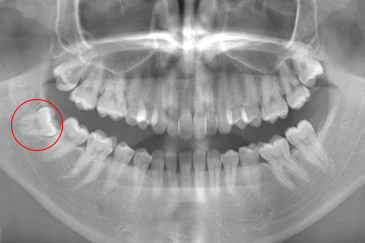

- お口全体のレントゲン撮影し確認します。

- 親知らずの形の確認と神経との位置を把握し安全に抜歯するため三次元のCTを撮影します。

現在の治療費と異なる場合がございます。最新の治療費は料金表をご確認ください。CASE 1

事前にCT撮影を行い神経との位置関係を確認して抜歯を行いました。右下親知らずは歯ぐきの中に完全に埋まり、

また斜めに生えていた為歯ぐきを切って親知らずの頭部分を分割して抜きました。

翌日多少の腫れが見られましたが痛みも痛み止めを飲めば過ごせる程度で出血はほとんどありませんでした。

抜歯前

抜歯後

基本情報

| 年齢・性別 | 24歳・女性 |

|---|---|

| 主訴 | 右下の親知らずが抜きたい |

| 治療内容 | 完全埋伏抜歯 |

| 治療期間 | 60分 |

| 治療費 | 約8,000円 |

| リスク・副作用 | 2〜3日は腫れと痛みがある。 必要に応じて抜歯を2回に分けて行う場合がある。 |